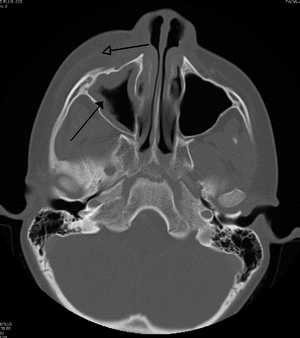

A computed tomograph showing infection of the ethmoid sinus

Frontal sinusitis